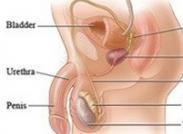

臍尿管未閉導致臍尿管瘺臨床較罕見,以臍孔漏尿為主要特征,并發(fā)感染時可出現局部癥狀。膀胱內注入亞甲藍觀察漏出液有否藍染,瘺孔內注入造影劑、排泄性膀胱尿道造影或膀胱造影可確診。治療方法為手術切除瘺管,由于部分患者可能存在下尿路梗阻,應注意解除梗阻。